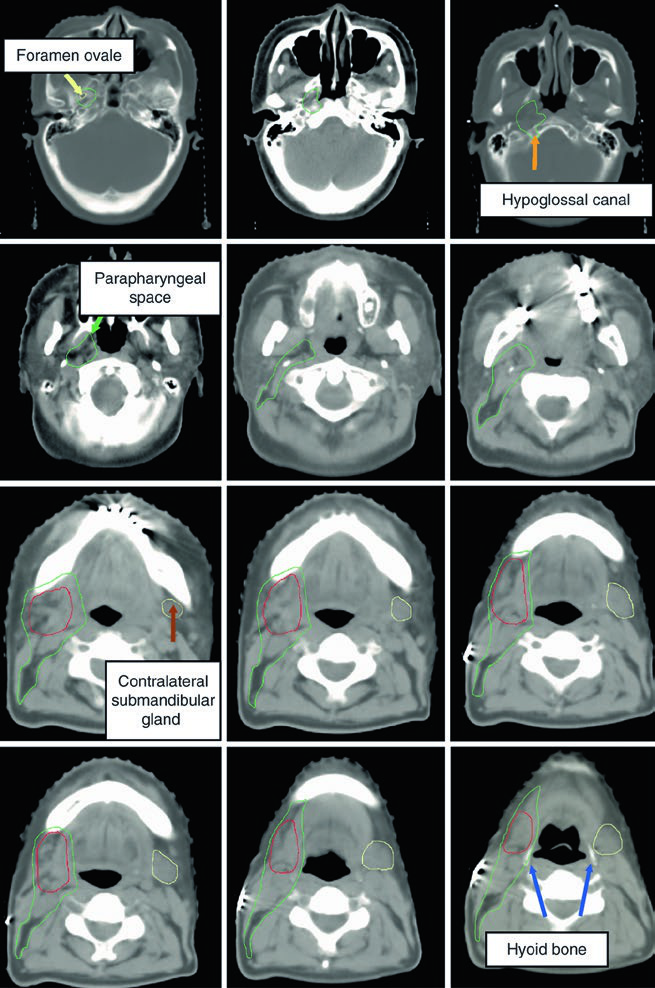

The parapharyngeal space is a predominantly fat-filled region extending from the skull base to the hyoid bone. Large or deep parotid tumors require its inclusion in the CTV60. Posterolateral to the styloid process lies the retrostyloid space, which may harbor lymph nodes and should also be incorporated into the treatment volume.

Skull base structure delineation must be performed using bone windows on CT. Key landmarks include: the foramen ovale (red), cochlea (blue), vestibule (orange), internal auditory canal (violet), and semicircular canals (green). Correctly identifying these structures is critical for ensuring adequate neural pathway coverage without excessive irradiation of sensitive structures such as the cochlea.

Submandibular tumors carry specific considerations for postoperative delineation. The entire surgical bed must be included along with all visible postoperative changes on the simulation CT. The intact contralateral submandibular gland serves as an invaluable anatomical guide for defining CTV boundaries.

The lingual nerve trajectory requires particular attention. It originates from the mandibular branch (V3) of the trigeminal nerve at the foramen ovale, courses deep to the lateral pterygoid muscle, then passes between the medial pterygoid muscle and the mandibular ramus, heading toward the medial aspect of the submandibular gland before terminating in the tongue. When the lingual or hypoglossal nerve is involved, the CTV must extend to the skull base — especially in adenoid cystic carcinoma.

The figure demonstrates a case of high-grade mucoepidermoid carcinoma cT1N1M0 of the right submandibular gland. The CTV60–66 (red) covers the surgical bed while the CTV50–54 (green) encompasses ipsilateral nodal stations and the parapharyngeal space up to the skull base. This ensures adequate coverage even in early-stage but high-grade tumors.